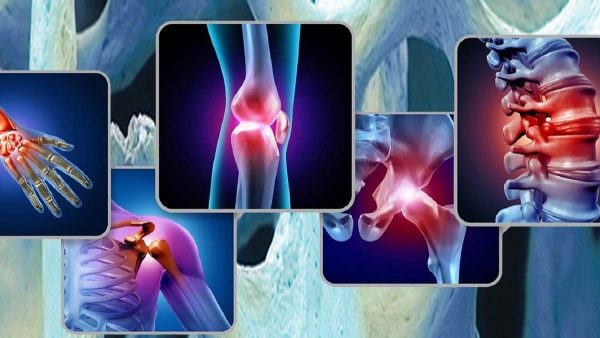

Let me give you some examples of chronic pain that I see in the Dee Why practice:

- A person presents to the clinic with chronic lower back pain, they have seen a number of practitioners who have given them little or no help. Generally the lower back has been the main area of focus in treatment. It needs to be said that the lower back pain may simply be a symptom of an underlying problem somewhere else.

- In this next example, a person presents to the clinic with a chronic knee problem. This person has again seen many different practitioners with little or no help. The focus of treatment has been the knee. Again in this case the knee pain may be only a symptom of problem somewhere else such as the foot or the hip. If we look at the diagram below, we can see the intimate relationship between the hip, knee and foot. There can be chronic tightness in the foot or hip, biomechanical dysfunction in how the foot or the hip moves or simply a lack of stability in the foot or hip due to injury or overuse. The foot or hip dysfunction can then lead to the knee having to work a lot harder which can than result in chronic pain. In this case the foot or hip would need to be treated along with the knee to resolve the chronic knee problem.